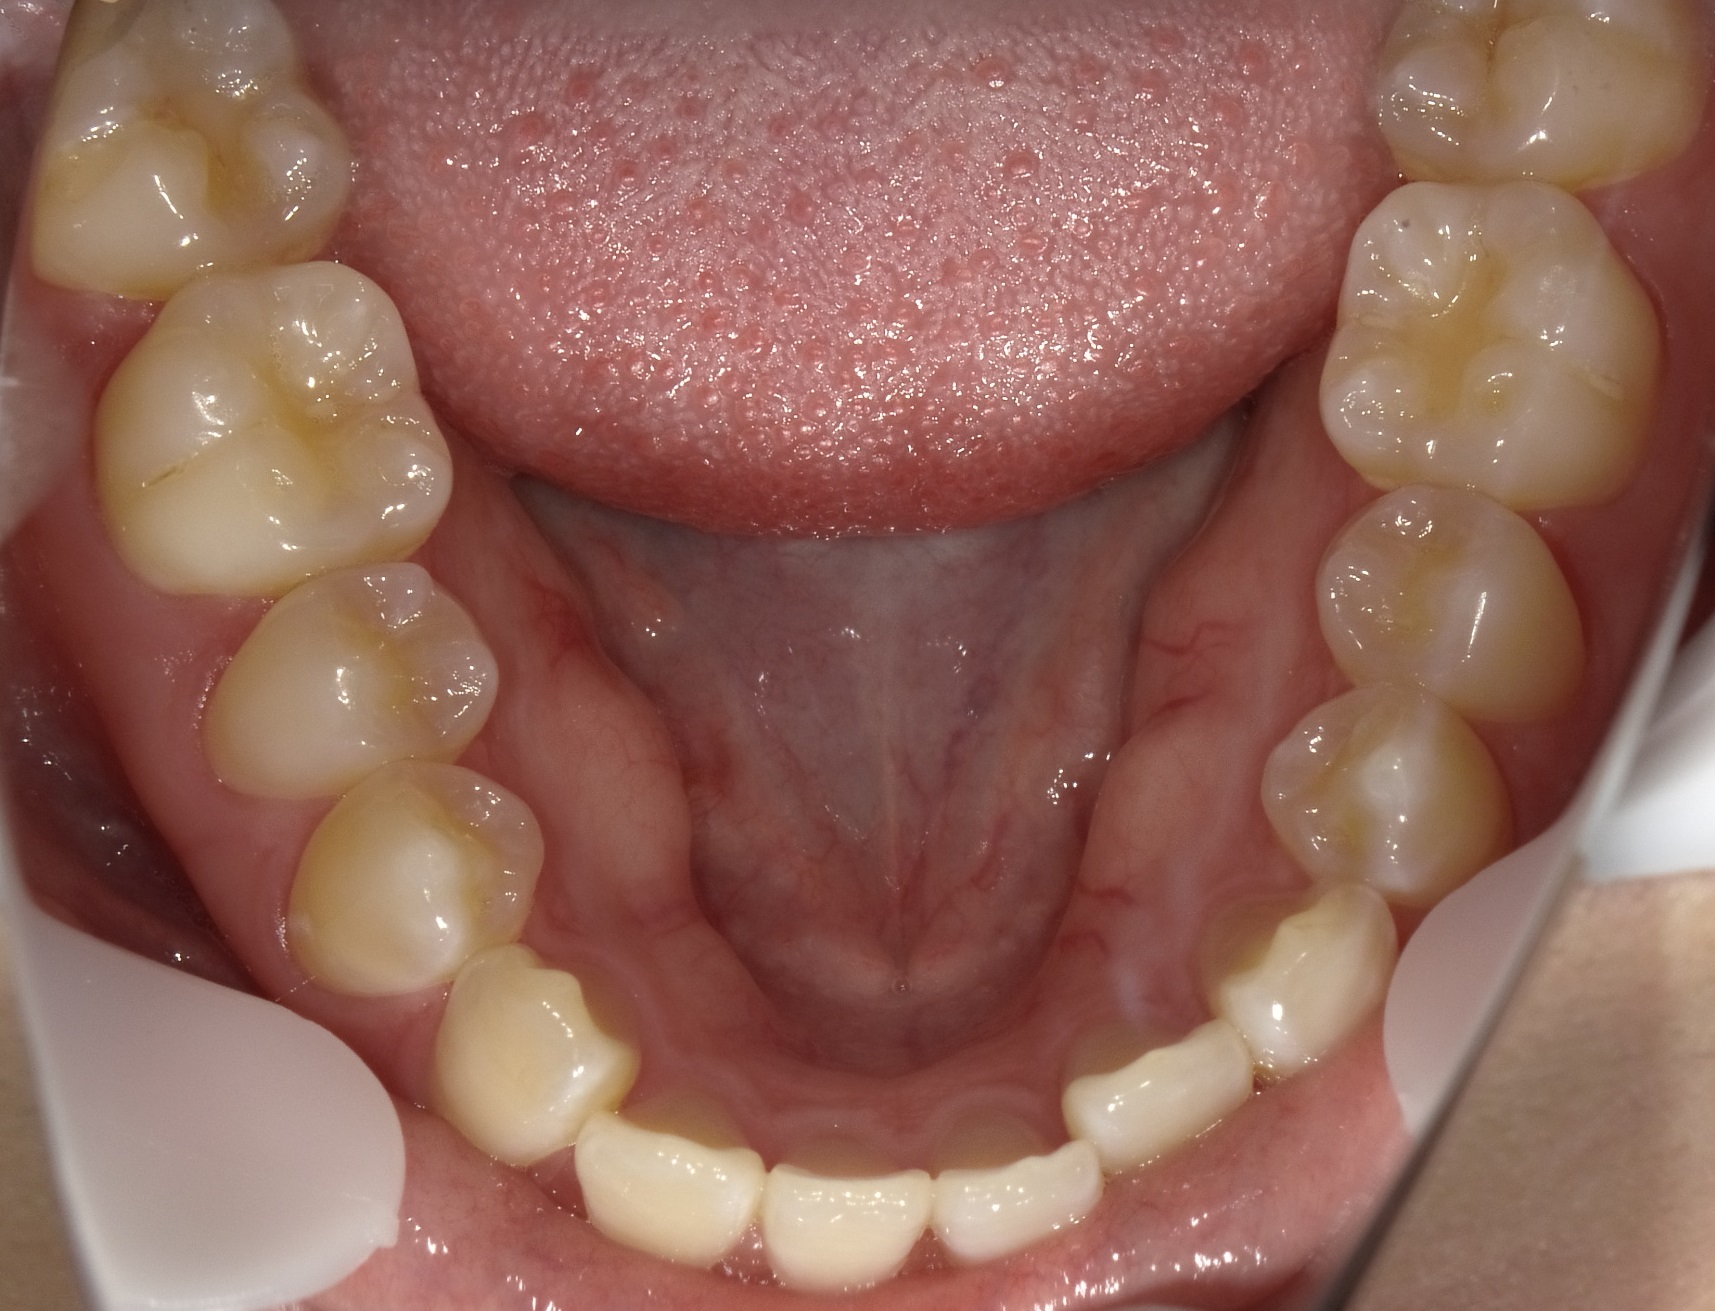

一方、下の歯を見てみると、下の親知らずが半分ほど頭を出しており上顎とは異なり、左下の前歯は通常より前に傾斜しています。

(写真上は見えませんが、少し親知らずが頭を出しています)

そのため今回は「左上の前歯が舌側に傾斜している」<「左下の前歯が前に傾斜している」ため、上の歯を治すために、下の歯を動かしていくことにしました。